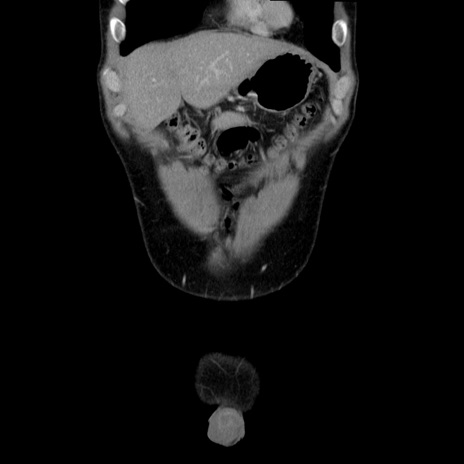

症例36(冠状断像)

【症例】20歳代 男性

【主訴】心窩部痛

【現病歴】今朝より上腹部痛あり。一旦軽快していたが再度出現したため救急要請。昨日夕に白身の魚を含む刺身を食べた。

【身体所見】BP 136/89mmHg、HR 74/min、BT 37.0℃、腹部:膨満、軟、心窩部に圧痛あり。反跳痛なし、筋性防御なし、腸雑音やや亢進あり。

【データ】WBC 17700、CRP 0.48